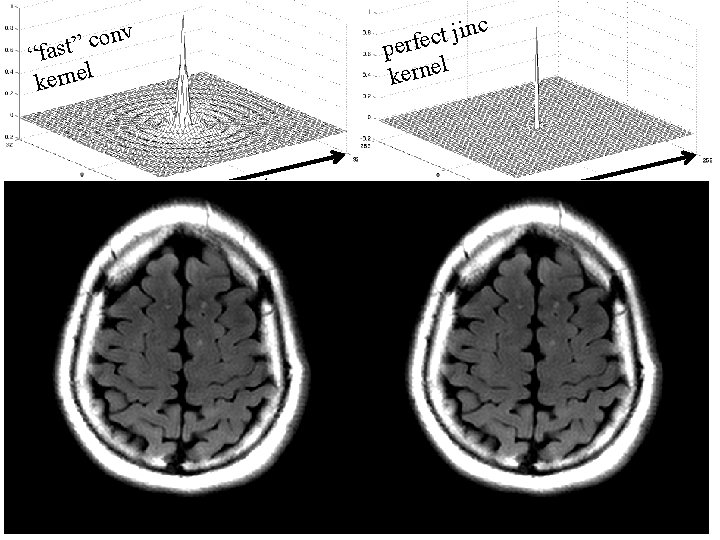

nc i j t c e perf l kerne v n o c “fast” l kerne 64 multiply image 256